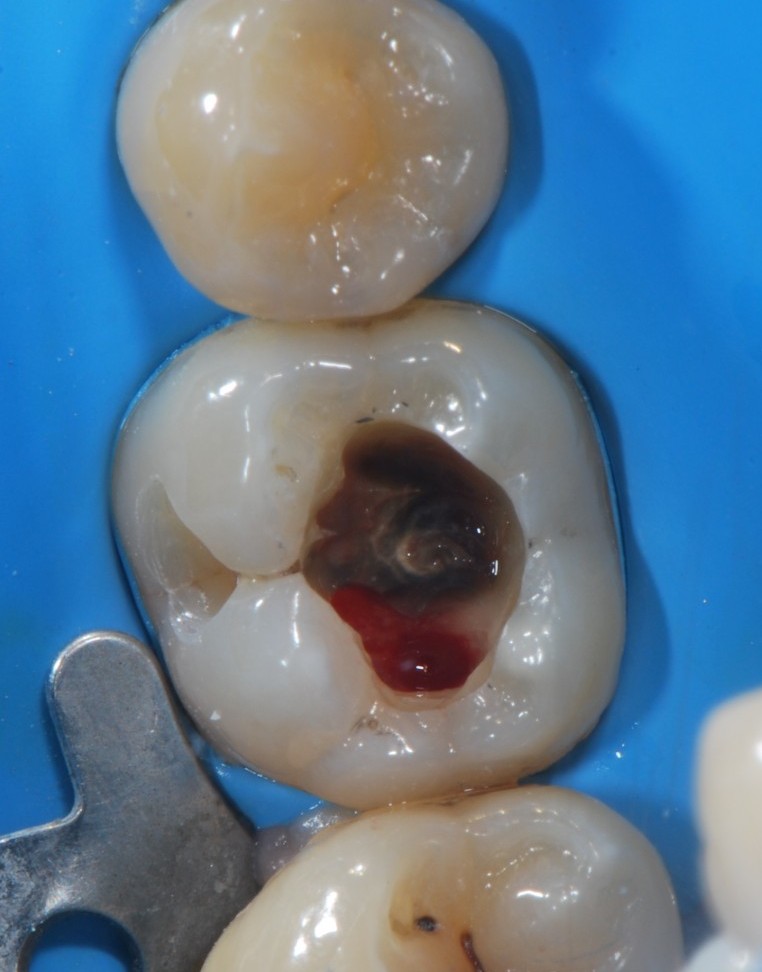

Quando ho aperto la cavità come per fare un’otturazione con mia somma sorpresa il dente sanguinava dove avrebbe dovuto esserci dentina! E non smetteva…???

Con un cucchiaino ho prelevato un po’ di quel misterioso tessuto, probabilmente impiantato da qualche alieno nel sonno, pensavo io, alla povera malcapitata e dopo aver fatto questo prelievo delicatissimo ho continuato a scavare fin dove potevo cercando un tessuto sano ma facendo estrema fatica a capire se a un certo punto mi trovavo sul nervo o se era ancora il dente a sanguinare.

Non volendo arrivare alla devitalizzazione, perché non avrei saputo come portarla a termine in mancanza della radice distale, ho fatto un’otturazione in composito.